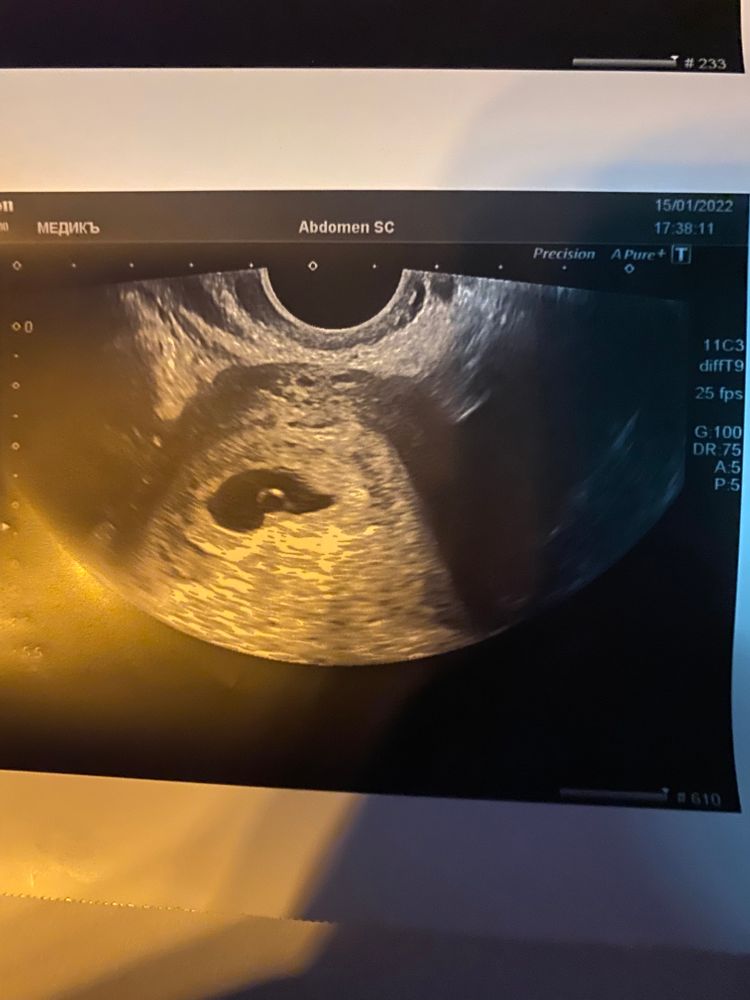

Вам эмбриональный срок поставили 3-4 это 5-6 акушерских,через неделю переделайте должен эмбрион появиться уже,ваше пя СВД -14,8 мм это на 6 акушерских примерно, овуляция если не отслежена могла быть не на 14 д.ц,а позже и поэтому все соответствует, ничего критичного не вижу

Алина , во-первых 6+3 это если овуляция на 14 д.ц,а если на 18 д.ц например,то срок по факту на 4 дня меньше,так как приложение и врачи считают срок по стандарту с овуляцией на 14 д.ц, во-вторых у вас пя 1,88*1,08 см,а это 1,88+1,08/2 и внутренний диаметр СВД пя получается 1,48 см или 14,8 мм что соответствует вашему сроку Изображение

Вам явно написали эмбриональный срок, а не акушерский. Так выглядит узи где-то на 6 акушерской неделе, на 3-4 у вас бы ещё плодное яйцо не рассмотрели.

Так у вас акушерский срок -5 недели и 6 дней, эмбриональный 3 недели 6 дней. УЗИ это и подтвердило. Все хорошо